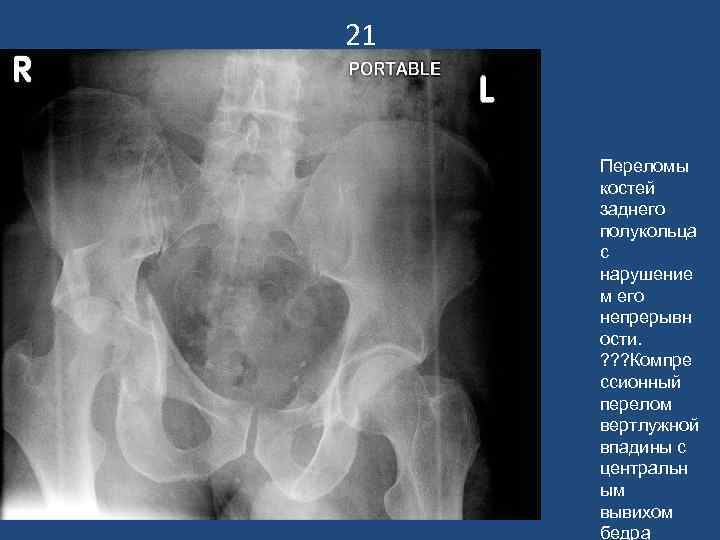

21 Переломы костей заднего полукольца с нарушение м его непрерывн ости. ? ? ? Компре ссионный перелом вертлужной впадины с центральн ым вывихом бедра